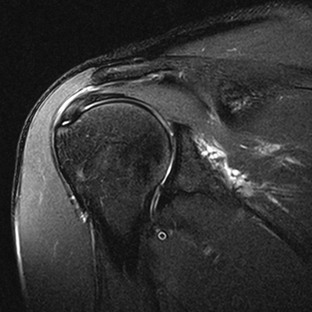

A full-thickness tear of the rotator cuff tendon is defined as a tear that extends through the complete thickness of the tendon from superior to inferior. This tear allows communication between the joint space and the subacromial-subdeltoid bursa. MRI criteria for establishing the diagnosis of a full-thickness tear include high (fluid) signal completely traversing the tendon from superior to inferior on T2-weighted images, a gap or absence of the tendon, and retraction of the musculotendinous junction (Fig. 44-21).

Rotator cuff muscles can undergo atrophy after tendon tears or after denervation. Denervation results in muscle edema followed by progressive fatty infiltration. Chronic rotator cuff tendon tears also result in muscle atrophy even if no nerve injury is present. The terminology with regard to atrophy of the rotator cuff musculature is confusing. The term fatty infiltration is typically used to describe actual fatty infiltration or replacement of the muscle, whereas muscle atrophy is used to describe a loss of muscle bulk. Muscle atrophy is seen on MRI as loss of muscle bulk (best depicted on sagittal images through the cuff musculature), whereas fatty infiltration is seen as streaks of high T1-weighted signal within the substance of the muscle (Fig. 44-22). When they are normal, the four muscles of the rotator cuff demonstrate symmetric bulk and signal characteristics. Loss of bulk indicates muscle atrophy, whereas streaks of high T1-weighted signal within the substance of the muscle indicate fatty infiltration. Goutallier and colleagues reported a system for grading fatty infiltration of the cuff musculature on the basis of CT imaging,108,109 and although this system has been widely adapted for use with MRI, a study by Fuchs and associates110 demonstrated poor correlation between CT and MRI with regard to grading fatty infiltration. Fatty infiltration is typically graded as mild, moderate, or severe based on the extent of fatty infiltration (high T1-weighted signal) with the belly of the muscle. Muscle atrophy can be graded separately as mild, moderate, or severe on the basis of muscle bulk depicted on sagittal images at the level of the supraspinatus fossa. Regardless of the terms used to describe muscle atrophy and fatty infiltration, they are associated with poor functional outcomes after rotator cuff tendon repair and increased risk of a repeat tear.111 Assessment of preoperative MRI scans should include evaluation of muscle atrophy.